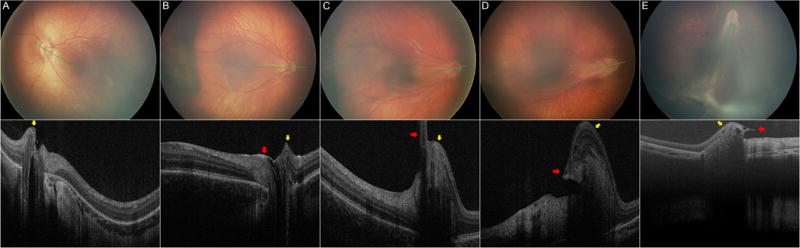

Figure 1.

Fundus photographs (upper) and corresponding optical coherence tomograms (lower) in five representative eyes of young children with FEVR and with optic nerve head dragging. From left to right the vitreopapillary dragging is possible (A) to a severe case with radial retinal fold (E). There is displacement of neurosensory retina (yellow arrows) toward the lesion side (mainly temporally) and upward. Note the evidence of strong vitreopapillary adhesion: focal posterior hyaloid thickening at temporal disc margin (B, red arrow) or vitreopapillary traction as evidenced by thick vitreous band at the leading edge of displaced retina (C–E, red arrows). In contrast, (A) had prior pars plana vitrectomy and showed no such attachment. Vitreopapillary adhesion is also observed in figure 2B.

In the 16 eyes with a nearly normal posterior fundus appearance on clinical examination and on fundus photographs, four eyes looked normal and 12 had ONH elevation (Figure 4) on OCT images. OCT findings in the eyes with ONH elevation included: 6 eyes with vitreopapillary traction or prepapillary membrane, 1 eye with mild ONH edema which was confirmed by leakage in fluorescein angiography, and 5 eyes with protrusion of the retinal vessels at the ONH (Figure 4). All 10 eyes with obvious or subtle ONH dragging on fundus photography had the following findings from OCT images:

Neurosensory retinal displacement: A displacement (or shifting) of the peripapillary neurosensory retina toward the peripheral fibrovascular lesion side. Because with OCT we could view both lateral and axial changes, we commonly observed that the peripapillary nasal retina was shifted temporally over the ONH and upward (towards the vitreous) at the ONH (Figure 1).

Retinal nerve fiber layer (RNFL) thickening at the temporal, superior and inferior disc margins, along with absence of outer retinal layers in the temporal peripapillary area above Bruch’s membrane leaving only RNFL at the temporal margin of the ONH (Figure 2).

Retinal elevation along the vasculature extending away from the optic nerve and on the side towards the peripheral pathology. The elevation was greatest at the area closer to the ONH and lowered as it extended farther away from the ONH (Figure 3). Retinal vessels were seen at the apices of these two elevations (Figures 3B, 3C, 3D). The retinal elevation was confined to the area around ONH in 6 eyes (Figure 1A, 1B, 1C) and extended beyond the posterior pole area but did not connect to the periphery in two eyes (Figure 1D). In one eye, the retinal elevation was connected with a peripheral fold to form a radial retinal fold (Figure 1E).

Strong vitreopapillary adhesion based on focal posterior hyaloid thickening at the temporal disc margin (Figure 1B, 2B) or visible vitreopapillary traction on OCT as evidenced by a thick vitreous band at the leading edge of displaced retina (Figure 1C, 1D, 1E), except in one eye which already underwent pars plana vitrectomy before the first imaging session.